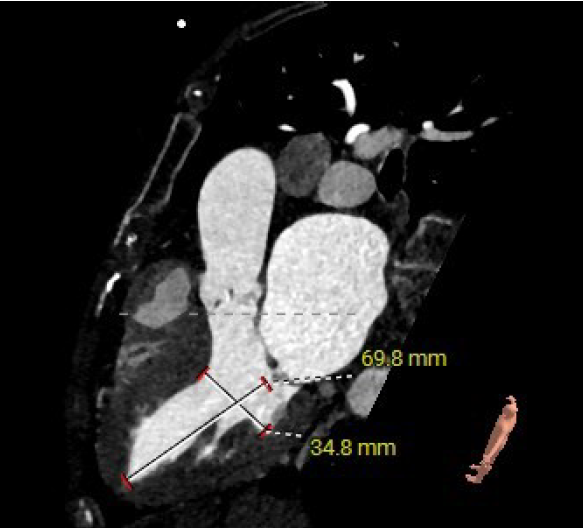

主动脉根部评估:

短轴

长轴

三叶式主动脉瓣;瓣环周长23mm,平均周长径72.1mm;左冠脉开口高度大于瓣叶长度;综合考虑冠脉风险低;LVOT周长径22.6mm;升主动脉直径32.1mm。

左冠高度12.1mm,右冠高度14.1mm;右冠脉开口高度大于瓣叶长度;SOV瓦式窦:平均周长径31.3mm;术中球囊预扩须密切注意冠脉灌注;STJ周长径26.5mm。